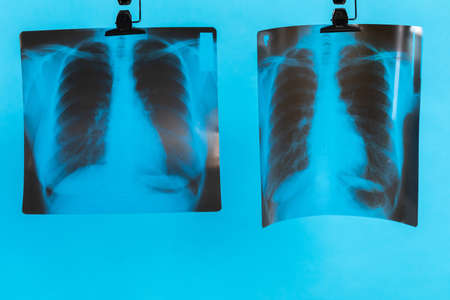

Lungs on a black and white photo taken on a photographic film of a special device.

Visualizing the Human Respiratory System with a D X-Ray Rendering. Concept Anatomy Visualization, Medical Imaging, X-Ray Diagnostics, Respiratory System Illustration, Radiology Technology